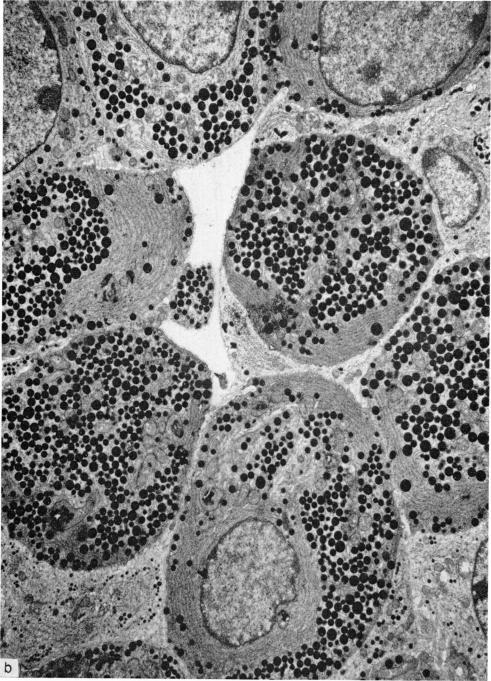

An electron microscopical study has been carried out to evaluate the effect of neonatal thymectomy on the hypophysis of germ-free mice at different times after the operation. The results fully confirm the previous findings in neonatally thymectomized, conventional mice. Also neonatal thymectomy in germ-free mice results in degranulation of growth hormone-producing cells in the anterior pituitary gland. A large number of these cells show an enlarged endoplasmic reticulum with formation of cisternae and loss of hormone granuli. This alteration of growth hormone-producing cells is similar to that observed in other cells of the hypophysis after removal of other target glands such as thyroid or gonads. The changes in the growth hormone-producing cells in neonatally thymectomized germ-free mice occur even in the first days after birth, when the number of differentiated growth hormone-producing cells is still very low. Some thymectomized germ-free mice showed symptoms of the wasting syndrome but the alterations in their hypophysis were not more pronounced than those observed in thymectomized germ-free but nonwasting mice. The data fit well our suggestion that the perinatal thymus is under hypophysial control and that immunological maturation depends on endocrine function.

已进行了一项电子显微镜研究,以评估新生期胸腺切除对无菌小鼠术后不同时间垂体的影响。结果充分证实了先前在新生期胸腺切除的常规小鼠中的发现。同样,无菌小鼠的新生期胸腺切除会导致垂体前叶中产生生长激素的细胞脱颗粒。大量这些细胞显示内质网扩张,形成池状结构,激素颗粒丢失。产生生长激素的细胞的这种改变类似于在切除其他靶腺(如甲状腺或性腺)后垂体其他细胞中观察到的改变。新生期胸腺切除的无菌小鼠中产生生长激素的细胞的变化甚至在出生后的头几天就会出现,此时分化的产生生长激素的细胞数量仍然非常少。一些胸腺切除的无菌小鼠出现了消瘦综合征的症状,但其垂体的改变并不比在胸腺切除的无菌但未消瘦的小鼠中观察到的更明显。这些数据很好地符合了我们的建议,即围产期胸腺受垂体控制,免疫成熟取决于内分泌功能。